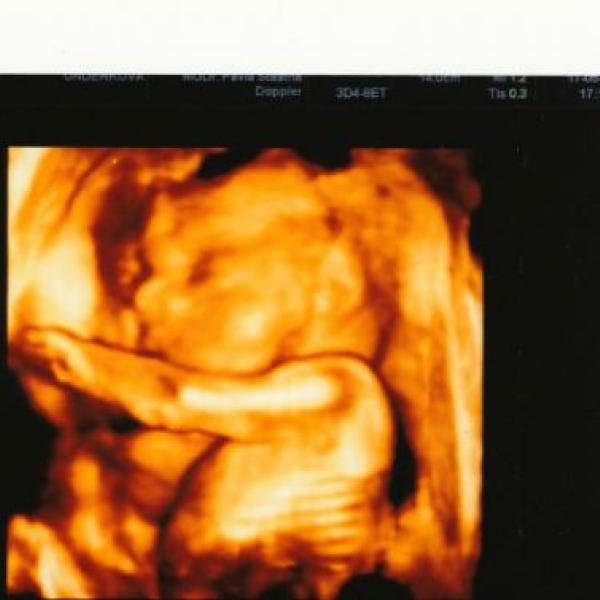

tak se mi poštěstilo vidět 3D utzv a naše milované miminko. Zatím je vše v pořádku a prý je to macík - 430 gr. nejdříve bylo k nám zády, pak se naštěstí umoudřilo a ukázalo se aspoň z profilu :-) jinak je to kluk jako buk :-) tak se všechny opatrujte :-) pááá